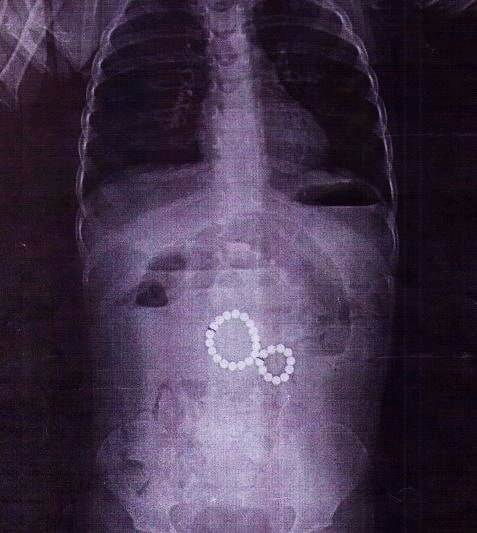

2-летняя девочка проглотила 29 магнитных шариков

Её прооперировали в Иркутской областной детской клинической больнице.

Сначала врачи поликлиники подозревали у ребёнка энтеровирус, но состояние ухудшилось: появилась непроходимость, сильная боль и рвота с кровью.

Рентген показал, что магниты соединились в «восьмёрку» и повредили кишечник, вызвав перитонит. Хирурги удалили все инородные тела и устранили осложнения. Сейчас малышка идёт на поправку.

❗️Врачи напоминают: даже два проглоченных магнита могут привести к тяжёлым последствиям. Родителям советуют не давать детям игрушки с магнитами, следить за мелкими предметами и при малейшем подозрении сразу обращаться к врачу. ИРСИТИ